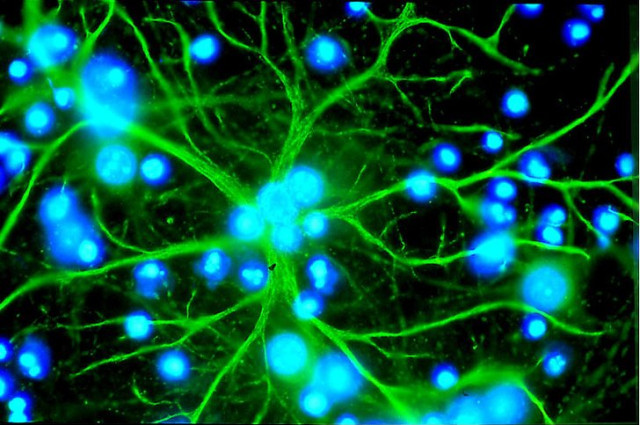

Стимуляція росту нових нейронів

Астроцити – клітини, які вдалося перетворити в активні нейрони.

При пошкодженні мозку порушені ділянки втрачають одну важливу здатність: нейрони в них більше не діляться, а, значить, не можуть відновлюватися. А ось гліальні клітини, що забезпечують побудову нейронних зв’язків мозку, в пошкодженій ділянці присутні. Отже, залишилося навчити їх перетворюватися в нейрони. І вченим це вдалося: вони створили особливу комбінацію молекул, що зробила перетворення. Отримані в результаті цього нейрони жили і функціонували в чаші Петрі більше півроку. У перспективі таблетка для зростання нейронів зможе допомагати людям, які відновлюються після інсульту, а також тим, хто страждає на хворобу Альцгеймера.